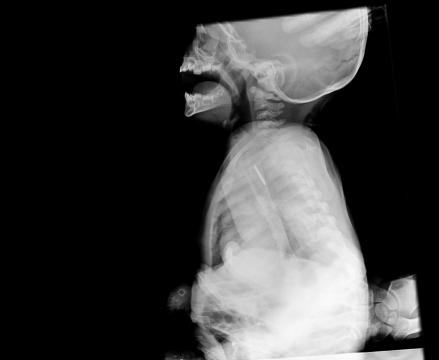

En av anledningarna till att axlarna åkt upp så mycket är nog röntgenbilderna. Det såg verkligen inte bra ut och det var inte svårt att förstå hur jobbigt det måste ha varit för stackars Morgan. Myntet ser verkligen stort ut i hans lilla kropp. Jag märker hur axlarna åker upp och andningen hamnar högre upp i bröstet på mig bara jag skriver om det. Ingen rolig känsla, så jag infogar bara bilderna så får ni själva fundera lite.

Nu är myntet ute och ligger alldeles svart i en liten platspåse (efter typ 3 veckor i Morgans matstrupe… 😦 och jag funderar på om vi skall sätta in det i en ram tillsammans med en printout av en röntgenbild, tillverka ett halsband av det eller göra något annat. I vilket fall skall vi spara det som en lycko-peng och en påminnelse om hur illa det kunde ha gått.